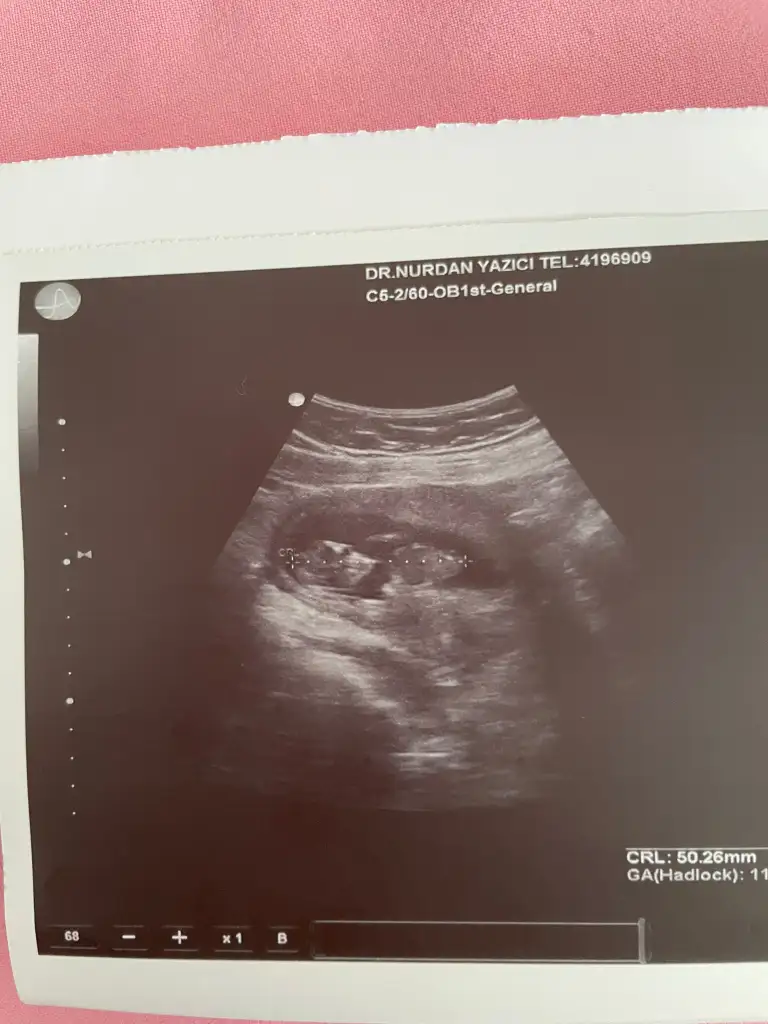

Kese fasülye şeklinde cinsiyet tahmini yapabilir miyiz

Kızlar cinsiyet tahmini yapabilecek var mı

Amin inşallah 🙏 sağolun 25 haftaligim halada doktor kesin birşey demiyor yüzde 90 kız ama bir cikinti var diyor bacak arası fotoğraflari bu sekilde